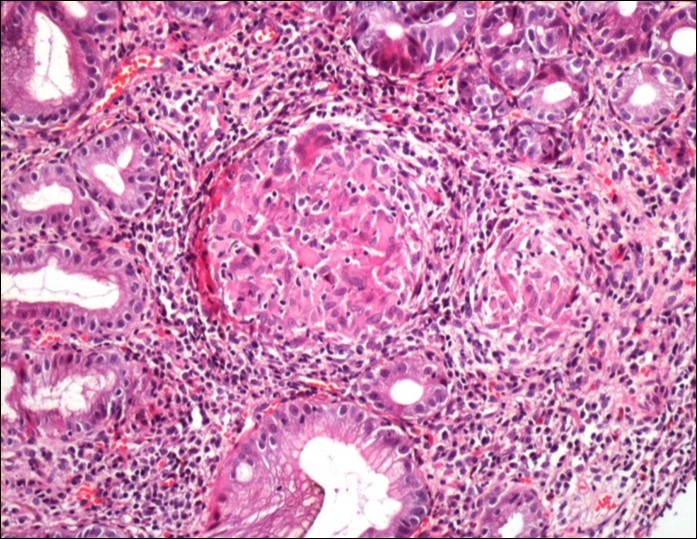

Concerning the etiology, diagnosis was made regarding to the past medical facts, the clinical symptoms, the endoscopic findings and the histological associated lesions. The main etiology was represented by Crohn’s disease in ten cases, followed by gastric tuberculosis in 6 cases. H Pylori was the retained cause of gastric granulomatosis in 5 cases, regarding to the absence of other etiologies, and the favorable issue after antibiotic eradication treatment. In 5 other patients, etiology of gastric granulomatosis was also found and the final diagnosis was a sarcoidosis (n=3), foreign body reaction (n=1), and yersiniosis (n=1). In our series, thirteen cases were unclassifiable despite etiological investigations and no cause of gastric granulomatosis was isolated. Histological findings of a case of tuberculosis and sarcoidosis are represented in Figure 1 and Figure 2.

Figure 2.Histological aspect of gastric granulomatosis secondary to sarcoidosis : Antral biopsy specimens revealing multiple non-necrotizing (sarcoid-like) granulomas ( HEx200)

Histological aspect of gastric granulomatosis secondary to             sarcoidosis : Antral biopsy specimens revealing multiple non-necrotizing (sarcoid-like) granulomas ( HEx200)